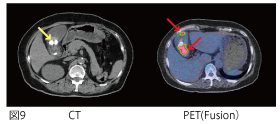

PET検査を行ったところ、肝臓の下にFDGの集積(図8↑)が見られました。横断面(図9)では、胆嚢の中にFDGの高集積が見られ、しかも二箇所に分かれて集積しています(図9赤↑)。さらに複数の胆石も認められました(図9黄↑)。